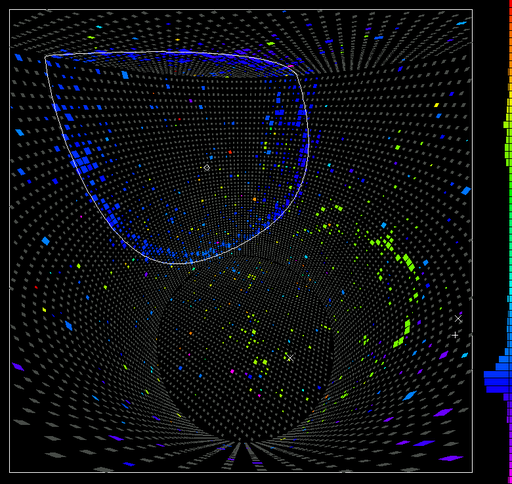

Brain regions from which it was possible to “read out” peoples’ intentions. In specific regions fine-grained patterns of brain activity showed slight differences depending on whether a person was preparing to perform an addition or a subtraction. From activity patterns in the green regions it was possible to read out covert intentions before subjects began to perform the calculation. From the regions marked in red it was possible to read out intentions that were already being acted upon.